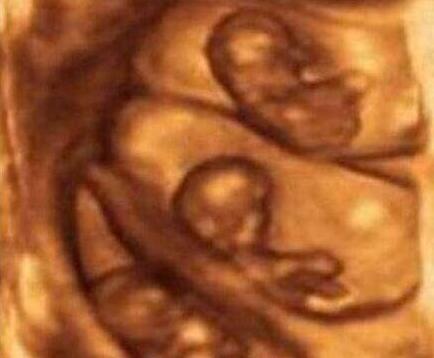

在2011年11月11日的时候印度一孕妇是产下了一11胞胎,看到上面的照片了吗?这就是流传出来的11胞胎照片和孕妈在怀孕时期的照片,简直是逆天啊,并且称这11个孩子都还是非常健康的存活了下来,不过关于此实例的真假并未得到证实!